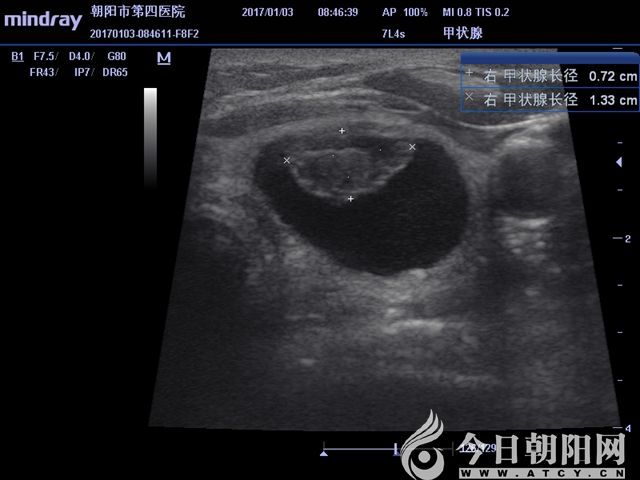

超聲測(cè)得實(shí)性結(jié)節(jié)大小

患者為65歲女性,發(fā)現(xiàn)左右側(cè)頸部包塊1個(gè)月,通過(guò)超聲檢查考慮甲狀腺腺瘤伴出血。患者從心理上不能接受頸部手術(shù)后切口瘢痕,拒絕手術(shù)切除,要求微創(chuàng)治療。針對(duì)患者要求,該院外科團(tuán)隊(duì)為其設(shè)計(jì)了治療方案——行甲狀腺微波消融術(shù)。手術(shù)采用局麻,在超聲影像引導(dǎo)下,順利準(zhǔn)確穿刺,抽出積血后,再于實(shí)性病變處用活檢針穿刺取病理,證實(shí)良性病變。